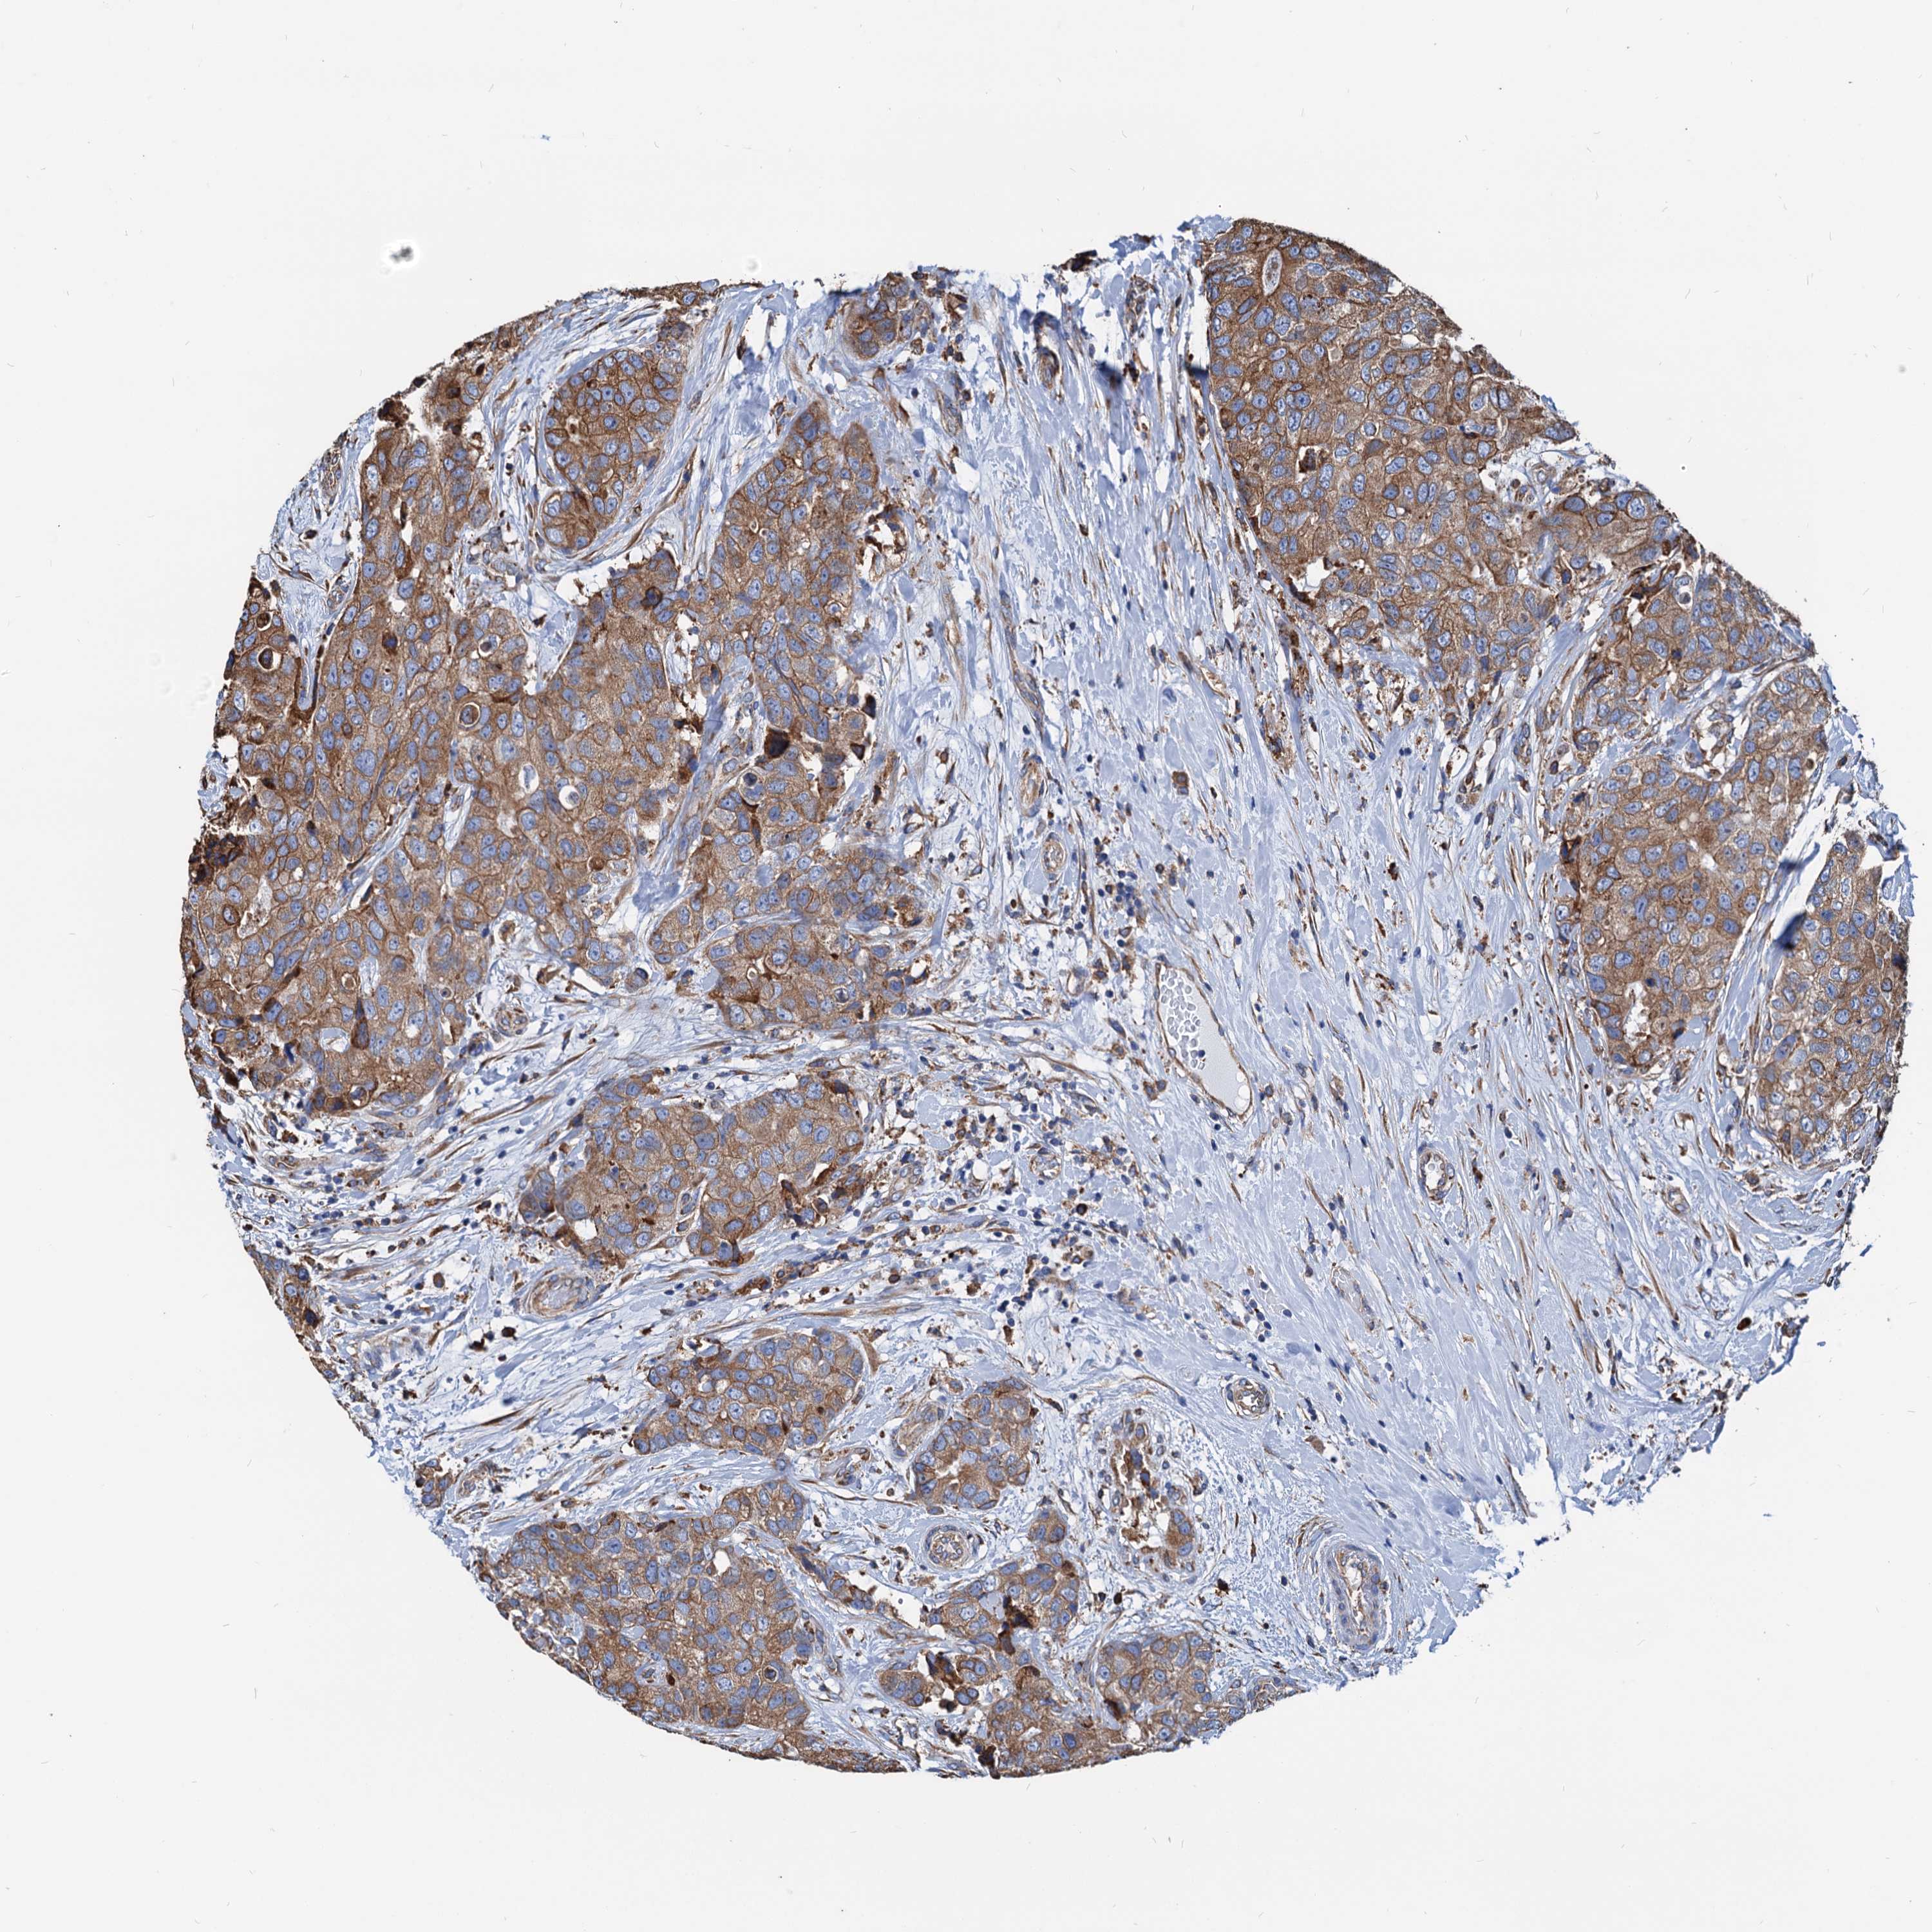

CANCER BREAST CANCER Show tissue menu

BRCA TCGA BRCA VALIDATION PROTEIN EXPRESSION

Breast cancer

Human cancer